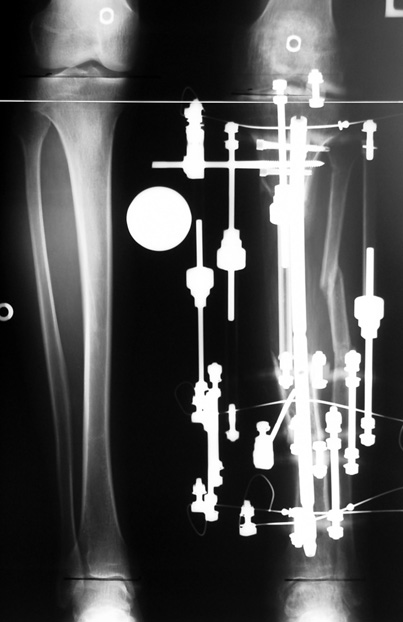

Appropriate radical debridement necessitates excision of all necrotic bone and soft tissues, and frequently causes instability at the involved extremity. The remaining bone and soft tissue defect has to be fixed and reconstructed. The distraction osteogenesis method of Ilizarov is used successfully for achievement of union, correction of the deformity, elimination of limb length inequality and reconstruction of segmental bone defects.

The duration of external fixation (external fixation index) depends on the amount of distraction required, and the extremity is prone to complications during this period. After the distraction phase is completed, the external fixator remains in place during the consolidation phase, which lasts twice as long as the distraction phase; but this period is hardly tolerated. If the external fixator is removed before sufficient consolidation is achieved, fractures, deformity and shortness will be the result. In our department, ‘lenghthening over nail’ method is used in order to decrease the external fixation index and increase patient comfort and activity level. In this method, the intramedullary nail is statically locked after the completion of the distraction phase, and external fixator is removed. The extremity is stabilized by the intramedullary nail during consolidation phase. In this way, complications due to long external fixation index or early removal of the external fixator are avoided.